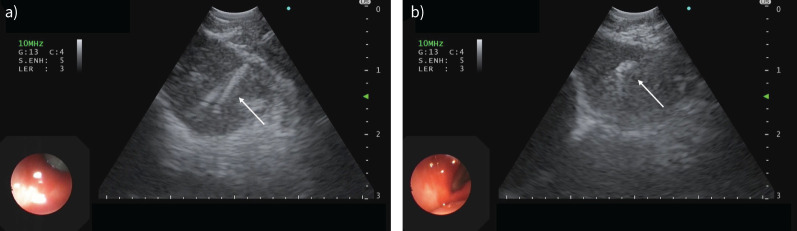

A 69-year-old man with generalised lymphadenopathy, glandular swelling and pleural effusion.

Patients with multisystemic presentation including respiratory symptoms and generalised lymphadenopathy should alert the clinician to this potential diagnosis https://bit.ly/4eJ0PHT.